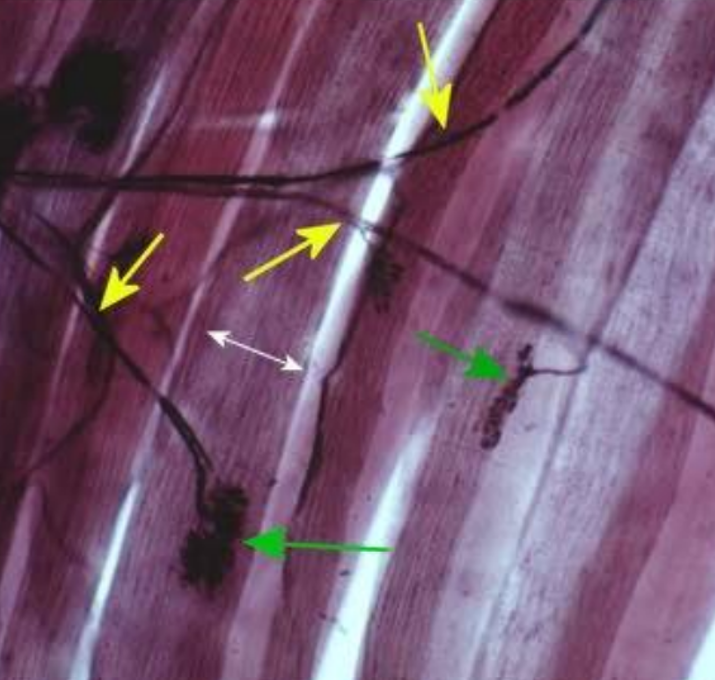

What is the pointer on?

Axon of a somatic motor neuron

What are the GREEN arrows pointing to?

Neuromuscular Junction

What are the YELLOW arrows pointing to?

Axon of a somatic motor neuron.

What is the WHITE arrow pointing to?

skeletal muscle fiber